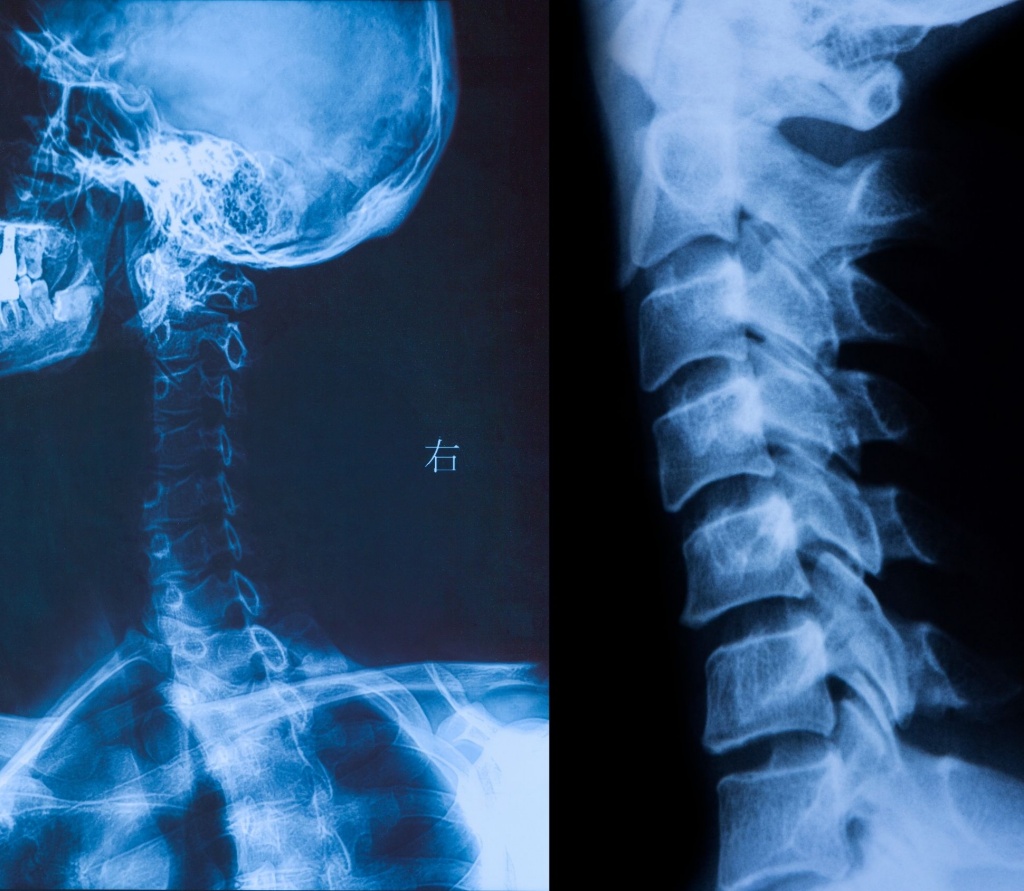

Шийний відділ хребта – одна з найвразливіших зон нашого тіла. Саме тут проходять судини, що живлять мозок, нервові корінці, які відповідають за чутливість і рухи рук, і структури, від яких залежить самопочуття, концентрація, сон. Біль у шиї, скутість, головний біль, запаморочення чи оніміння пальців – це не «дрібниці», а сигнали, які варто перевірити.

Рентген шийного відділу хребта – базове, інформативне та доступне обстеження, яке дозволяє оцінити стан хребців, міжхребцевих проміжків і фізіологічних вигинів.

Що показує рентген шийного відділу хребта

Рентгенографія дає змогу лікарю побачити:

-

зміщення хребців;

наслідки травм (тріщини, переломи, підвивихи);

дегенеративні зміни (остеохондроз, спондильоз);

викривлення шийного відділу;

зменшення висоти міжхребцевих дисків;

ознаки нестабільності хребта.

Це дослідження часто є першим кроком у діагностиці перед призначенням лікування або додаткових методів обстеження.

Процедура займає лише кілька хвилин і не потребує спеціальної підготовки. Дослідження проводиться у кількох проєкціях – це дозволяє максимально точно оцінити стан шийного відділу.